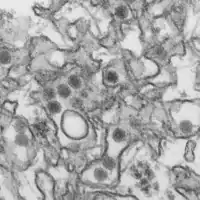

![]() Електронна мікрофотографія вірусу Зіка. | ||||||||

Вірус Зіка відносять до роду Flavivirus, родини Flaviviridae. Містить РНК, належить до групи ІV — позитивно спрямованих одноланцюгових РНК-вірусів з складною трансляцією. Вірус Зіка є одним з двох видів вірусів з клади Спондвені (англ. Spondweni)[12]. Станом на 2016 рік розрізняють дві генетичні лінії вірусу Зіка — африканську, що має обмежену циркуляцію в Центральній Африці, та азійську, яка циркулює на широких теренах від Південно-Східної Азії до Америки, забезпечуючи основний приріст випадків хвороби через пандемічне поширення[13].